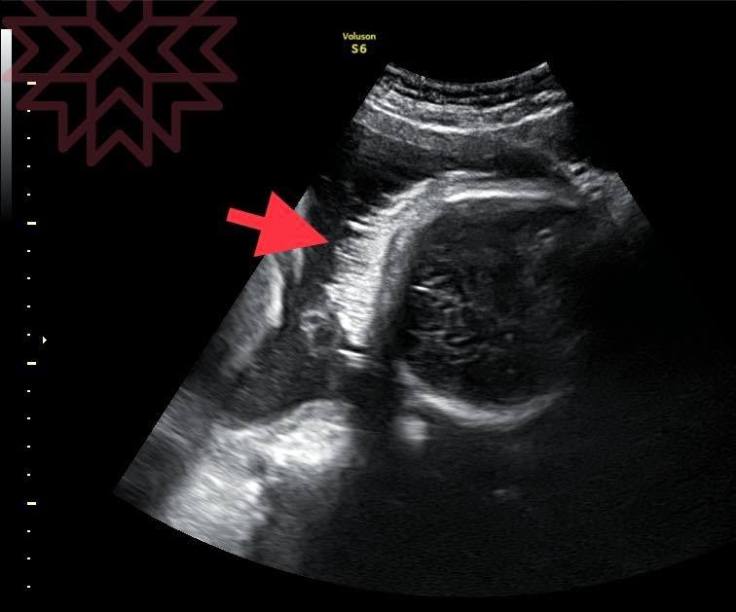

頭髮就在超音波照片箭頭指的這裡嘍

如果用動態檔你會看到頭髮還會飄呢